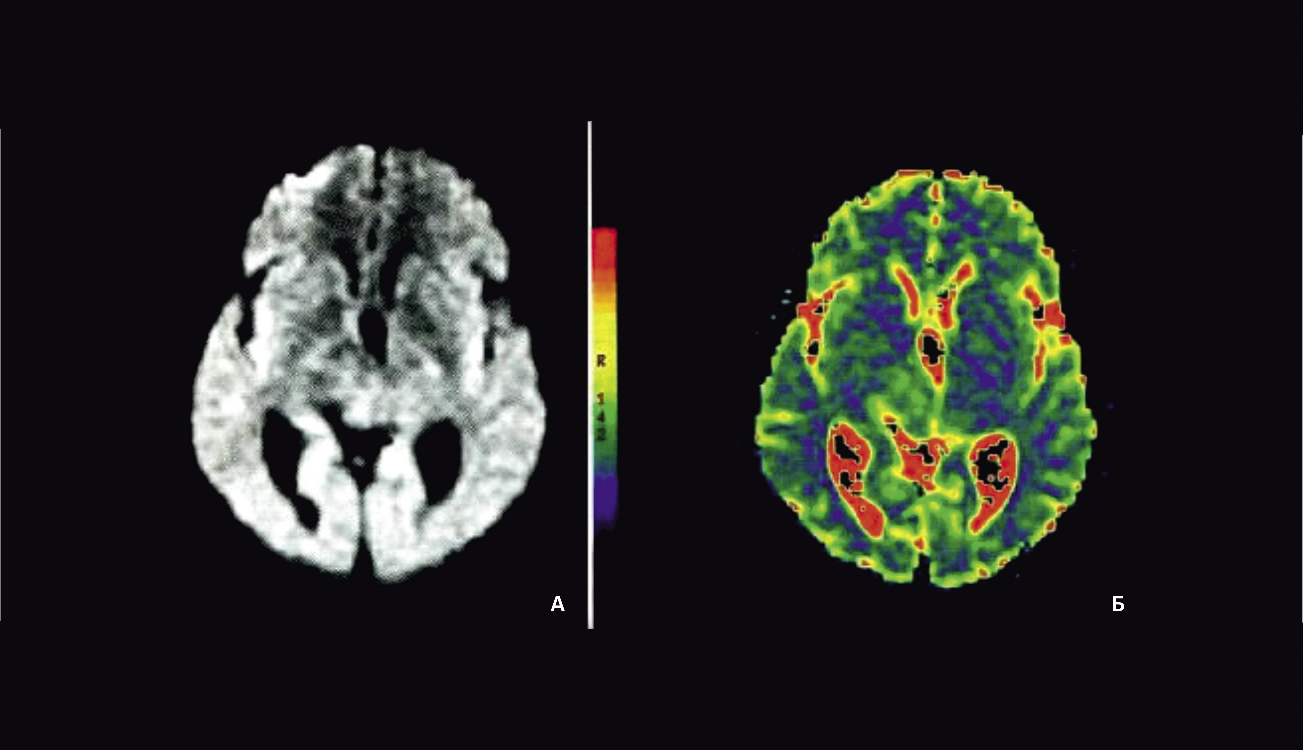

Диффузионно-взвешенная МРТ является одним наиболее быстрых, неинвазивных и информативных методов диагностики церебрального ишемического инфаркта без введения контрастного вещества на самых ранних его стадиях (в течение первых минут после сосудистой катастрофы) и дальнейшего наблюдения за развитием патологических изменений в тканях головного мозга [5; 18]. Оперативное определение признаков ишемического поражения церебральной ткани (до 6 часов) позволяет использовать временной промежуток так называемого терапевтического окна для тромболизиса и частичного или полного восстановления кровотока в пораженных тканях мозга. Данный вариант МРТ (рис. 1) позволяет дифференцировать свежие сосудистые очаги от более старых по относительной гиперденсивности (повышенной интенсивности) первых [24] и тем самым определять формирование повторного инфаркта головного мозга на фоне существующих постишемических изменений, что имеет большое практическое значение для выбора тактики ведения больных после инсульта (табл. 1).

Рис. 1. Диффузионно-взвешенная МРТ головного мозга А: диффузионно-взвешенное изображение; Б: диффузионная цветовая карта на этом уровне